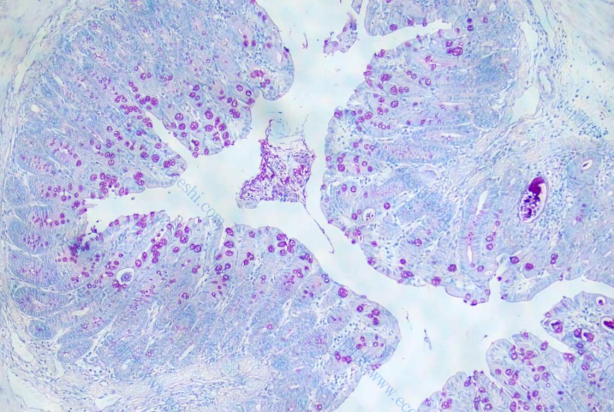

1、HE染色

7、AB-PAS染色